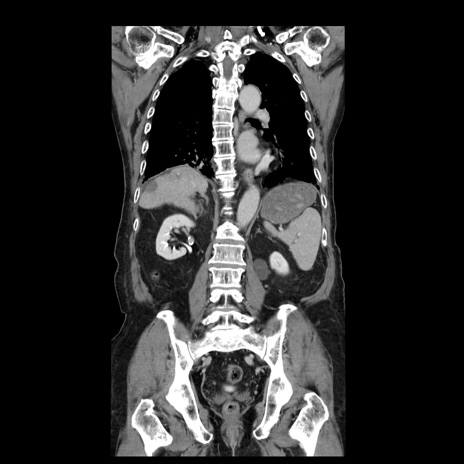

症例21(冠状断像)

【症例】70歳代男性

【主訴】腹痛

【現病歴】肝硬変・肝細胞癌にてかかりつけの方。約9時間前に食後より腹痛出現。症状が徐々に増悪し、嘔吐出現したため来院。

【既往歴】肝硬変、肝細胞癌(RFA、TACE後)

【身体所見】意識清明、表情苦悶様、BT 36℃、BP 129/78mmHg、P 88bpm、SpO2 97%(RA)、右上腹部から心窩部にかけて圧痛あり、反跳痛なし、筋性防御あり。

【データ】WBC 5800、CRP 0.16